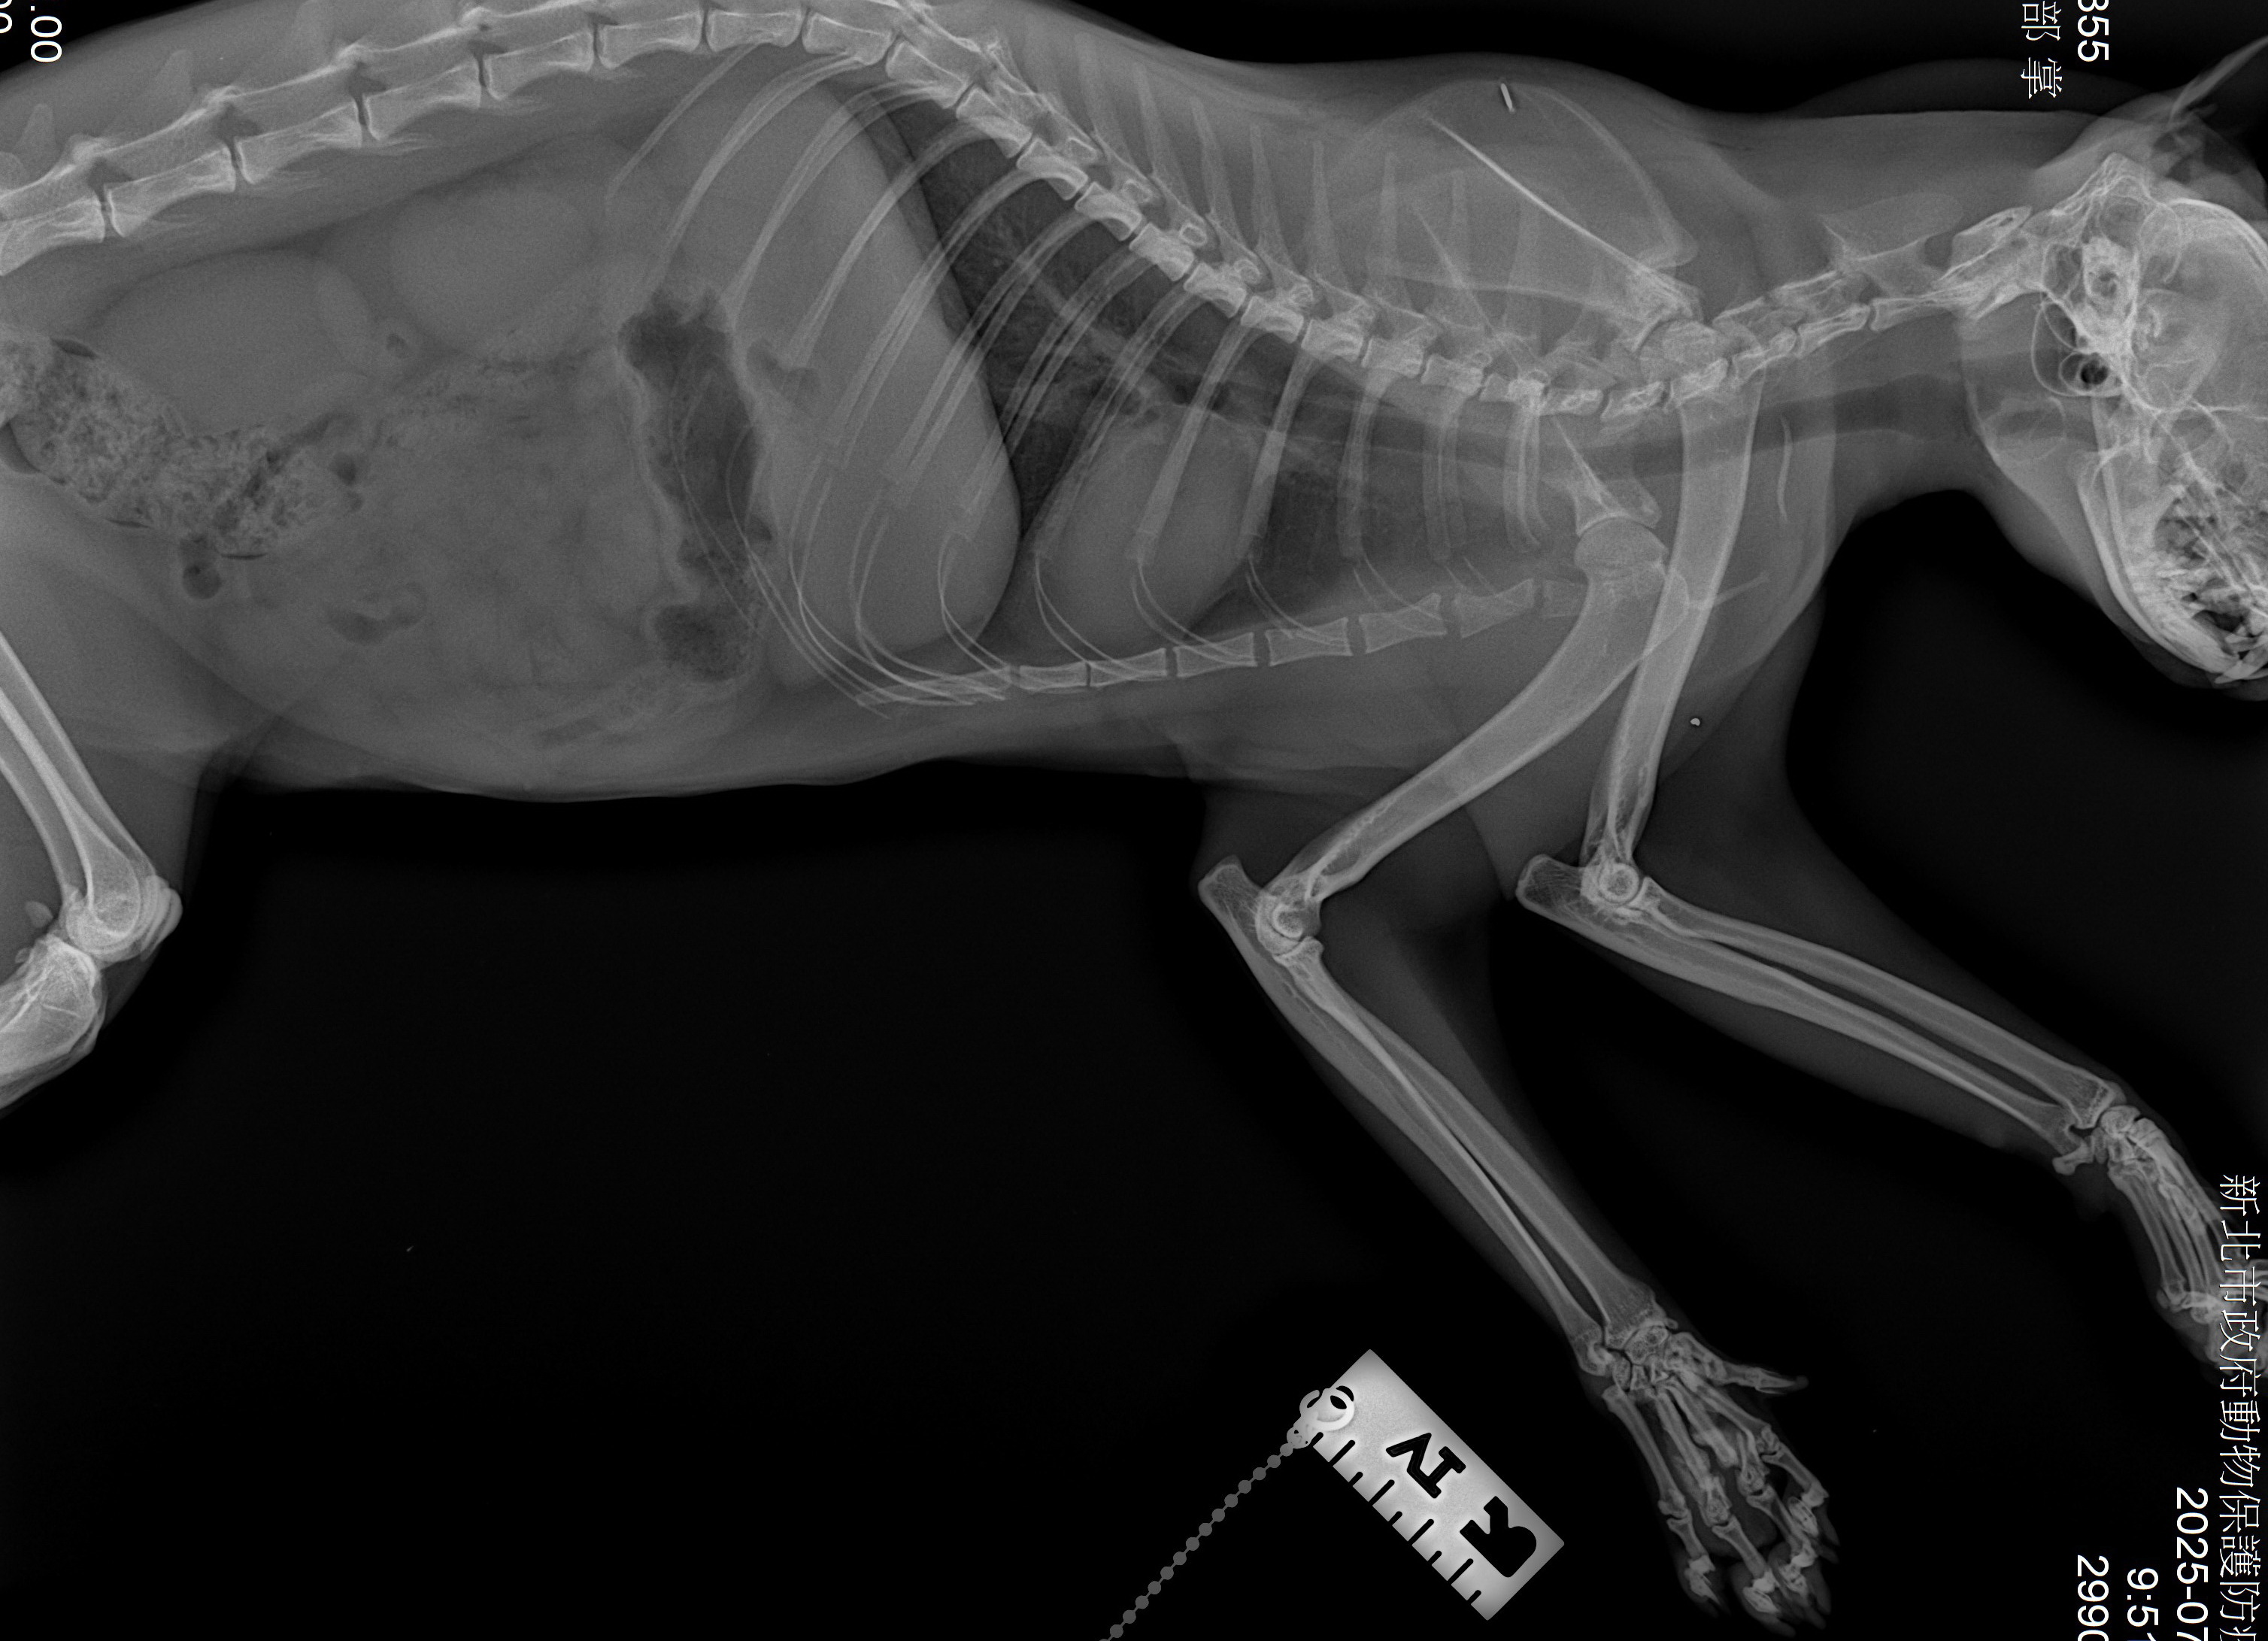

【新北市訊】新北市動保處日前接獲通報汐止區茄冬路有隻白色虎斑貓,疑似車禍受傷臉部髒污癱臥路旁,動保處隨即派員將受傷白虎斑貓帶回毛寶貝醫療中心進行檢傷醫療,經醫療中心李獸醫師檢查後,發現白虎斑貓全身癱軟、左眼角及左下頷部位有傷口、X光檢查下可見雙前肢掌骨有斷裂傷,應該是高空摔落或車禍所造成,白虎斑貓經過緊急輸液治療及加強肢體復健後已恢復健康,由住在汐止的蔣小姐認養,有了幸福溫暖的家。

動保處獸醫師李建沛表示,依毛寶貝醫療中心傷病動物案例顯示,貓咪常因為高空不甚摔落、車禍而造成不同程度的傷害,尤其以顏面受創及肢體骨折居多,若胸腔受創嚴重造成橫膈破裂,則須緊急進行手術治療才能避免猝死,這隻虎斑貓研判可能是高空不甚摔落,造成前肢掌骨斷裂及臉部受創,所幸臉部及骨折部位傷勢不嚴重,經過復健治療後已回復行走及跳躍功能,很高興牠找到了幸福溫暖的家。